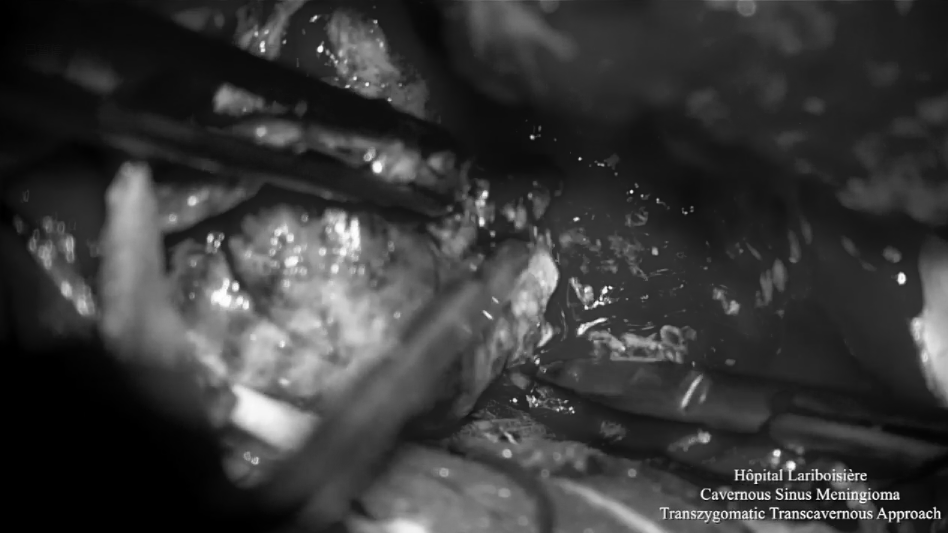

▼使用顴弓入路手術(shù),利用筷子技術(shù)神經(jīng)內(nèi)鏡+顯微鏡次全切除腫瘤,從海綿竇剝離硬腦膜,切除了浸潤的硬腦膜和向顳部延伸的硬膜上腦膜瘤。

使用顴弓入路手術(shù),利用筷子技術(shù)神經(jīng)內(nèi)鏡+顯微鏡次全切除腫瘤,從海綿竇剝離硬腦膜,切除了浸潤的硬腦膜和向顳部延伸的硬膜上腦膜瘤。

▼顯微鏡下暴露海綿竇外側(cè)壁,注意暴露血管,并進行竇外腫瘤切除。

顯微鏡下暴露海綿竇外側(cè)壁,注意暴露血管,并進行竇外腫瘤切除。